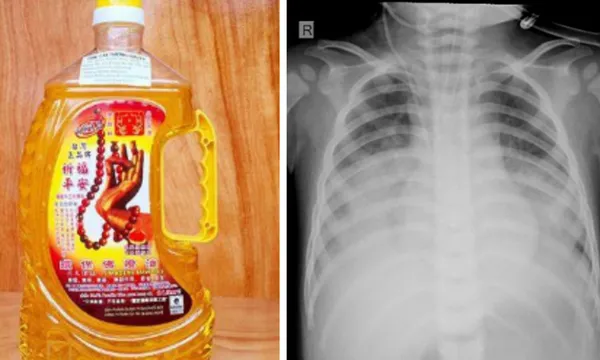

VOH - Ngày 29/12, khoa Hồi sức tích cực chống độc – Bệnh viện Sản Nhi Nghệ An cho biết, khoa vừa tiếp nhận một bệnh nhi bị ngộ độc do uống nhầm dầu thắp đèn dẫn đến viêm phổi nặng.

Bệnh nhi T.N.H (15 tháng tuổi, huyện Quỳnh Lưu) nhập viện trong tình trạng suy hô hấp, da tái, viêm phổi nặng…

Người nhà bệnh nhi cho biết, trước khi vào viện 2 giờ, bé uống nhầm dầu thắp đèn, sau uống trẻ bị sặc, ho, tím tái, khó thở.

Tại đây, bé nhanh chóng được các bác sĩ hỗ trợ hô hấp bằng thở máy áp lực cao cho trẻ, dùng kháng sinh phổ rộng… Hiện bệnh nhi vẫn đang trong tình trạng nguy kịch, cần theo dõi.